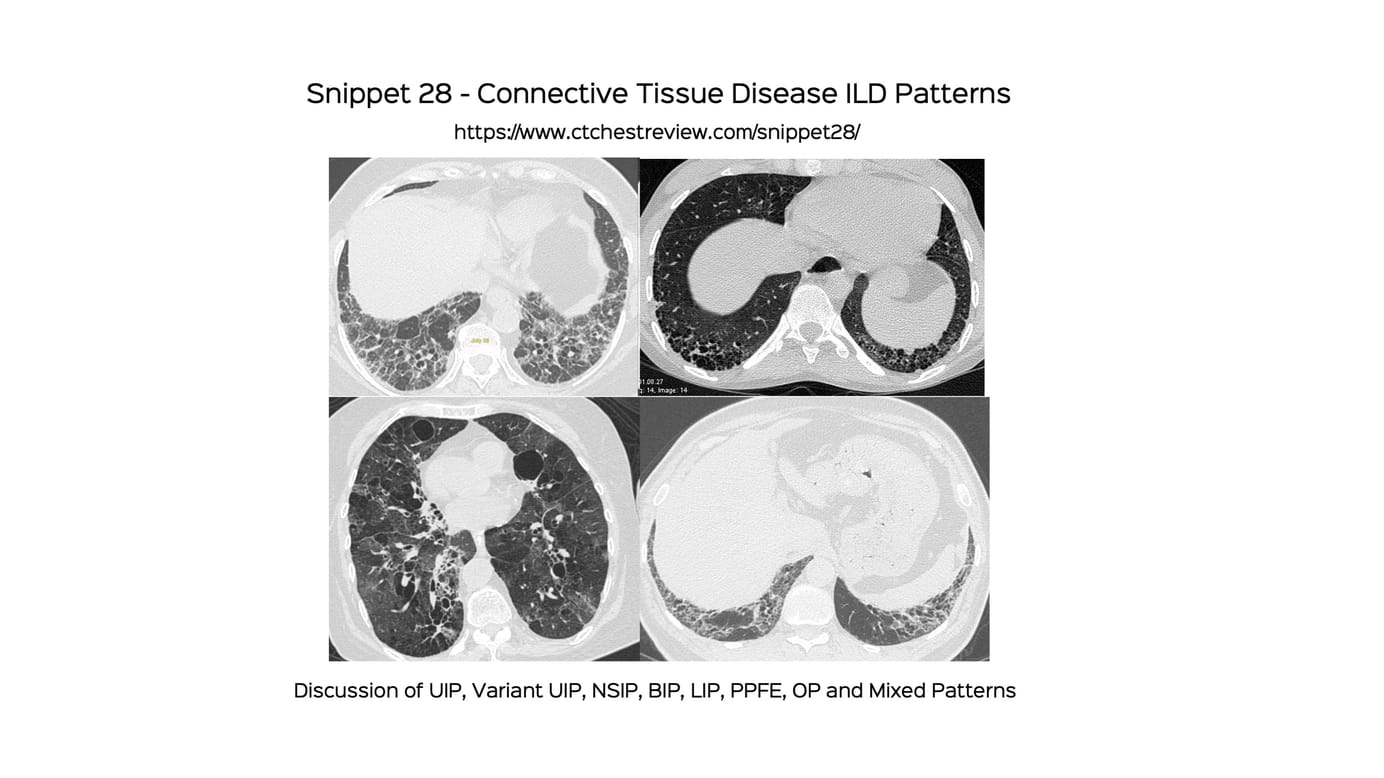

Snippet 28: Connective Tissue Disease ILD Patterns

A discussion of the various patterns seen in CTDs. UIP and variants, NSIP, BIP, LIP, PPFE, OP, mixed and rapidly progressive.

Over the last 1 year there has been a change in the understanding of the various patterns that we can see in patients with connective tissue disease (CTD) ILDs.

This snippet goes through the various patterns, including the new nomenclature of the BIP pattern and briefly discusses the rapidly progressive phenotype seen in the IIMs.